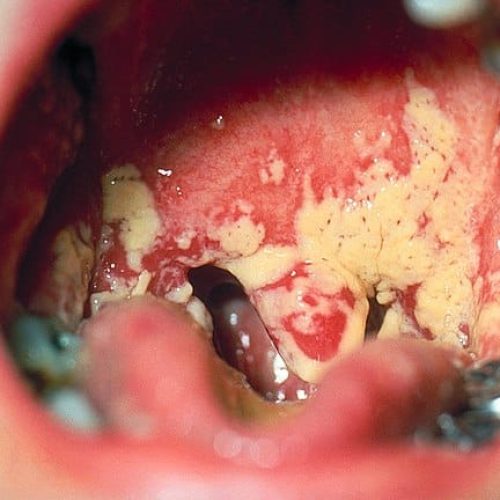

Bilder von Mundsoor

• Weißlicher Belag auf der Zunge, dem Gaumen, dem Zahnfleisch und der Innenseite der Wangen. Dieser lässt sich in der Regel abwischen, unter dem Belag ist die Schleimhaut gerötet.

• Entzündete rötliche und manchmal blutende Stelle